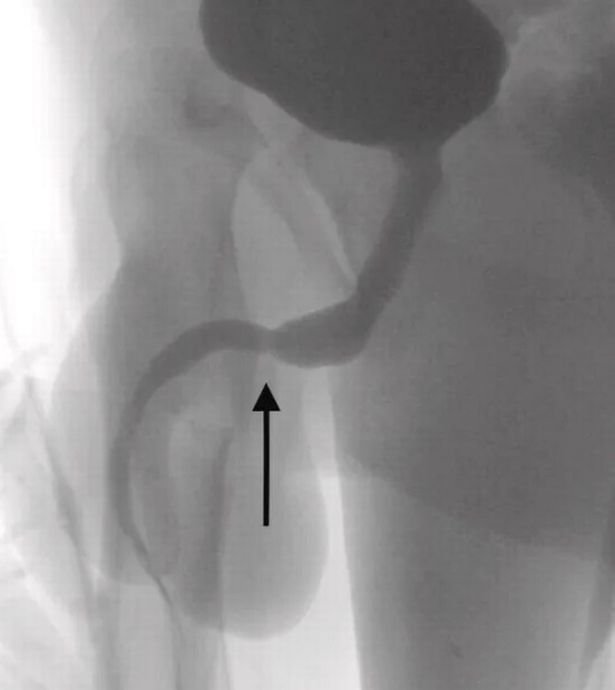

Yaşadığı olayı kaldırıldığı hastanede doktorlara anlatan gencin röntgen sonucunu inceleyen bilim insanları ise şaşkına döndü. “Cinsel deney” uğruna sağlığını riske atan gencin penisinden USB kablo zorlukla çıkarıldı.

Ameliyatı gerçekleştiren doktorlar durumu kamuoyuna hazırladıkları bir rapor ile duyururken, USB kablolarının vücut içinde düğüm olduğunu ve bu sebeple ameliyatın büyük bir zorluk içerisinde gerçekleştiğini açıkladı.

Science Direct isimli medya platformunun Urology isimli bilimsel dergiden hazırladığı haberde yer alan bilimsel araştırmada olayın 2021’de meydana geldiği belirtildi. Doktorların kaleme aldığı bilimsel araştırmada, “Vücuda yerleştirilen cisim derin doku üzerinden çıkarıldı. Kablolar penis ucundan çıkarıldı” denilirken ismi açıklanmayan gencin cinsel deney için bunu yaptığı ve herhangi bir zihinsel rahatsızlığı olmadığı da duyuruldu